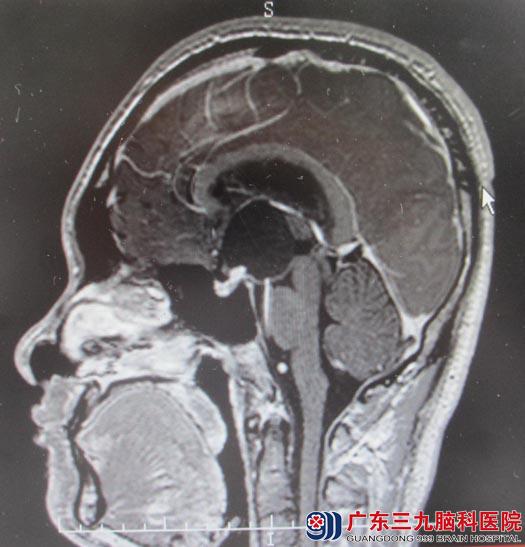

28岁的小舟一个月前开始出现头痛,头晕等症状。最近发作的频率逐渐增高,起初以为是工作压力大,疲劳导致,一直吃药调理,但不见好转。有一天在上班时突然出现剧烈头痛、呕吐、神志不清。被同事紧急送往医院,头颅MRI提示鞍区囊实性占位,颅咽管瘤可能性大,肿瘤大小为34.5mm×36.5mm×24.5mm,梗阻性脑积水。

▲手术前